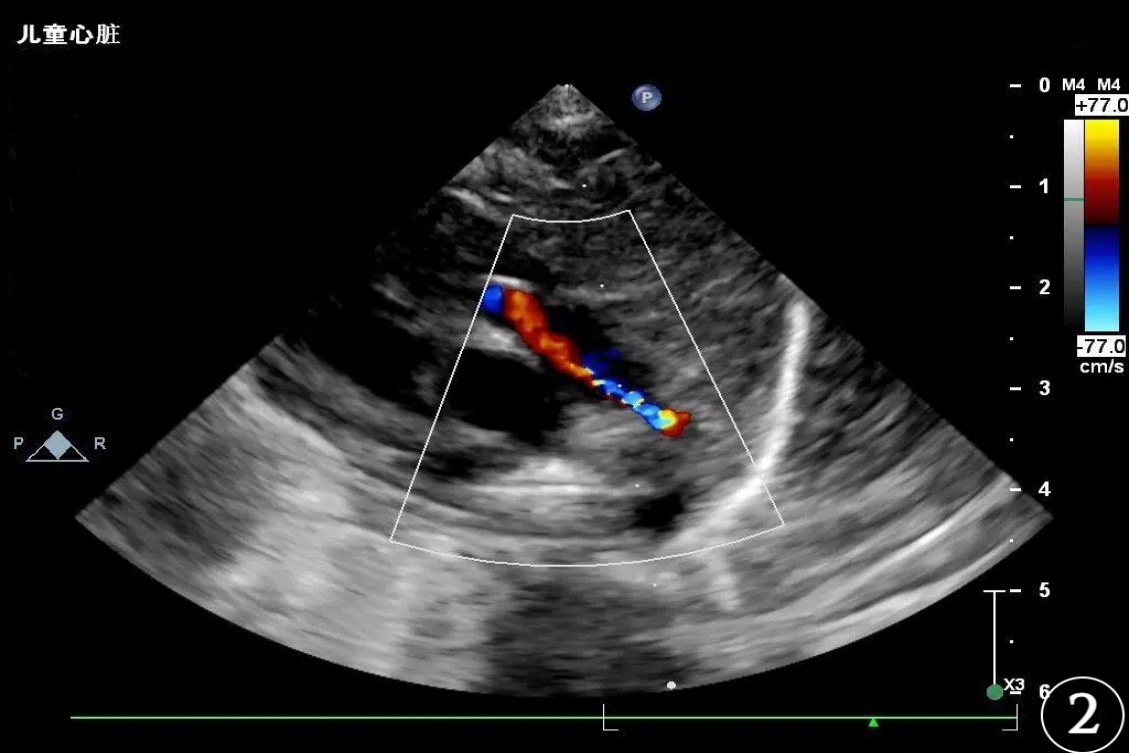

患儿,男,胎龄36周,出生体重3160 g,单胎,无窒息复苏史。系第2胎第2产,于暨南大学附属第一医院产科经阴道分娩娩出,出生时羊水清,自然啼哭,肤色稍青紫,反应、肌张力可、听诊心率 > 100次/分,Apgar评分:生后1 min为9分(肤色扣1分)、5 min、10 min均为10分。脐带水肿,绕颈一周,胎膜、胎盘无异常。血糖:3.0 mmol/L。血型:O型Rh阳性。其母血型为O型Rh阳性,妊娠期糖尿病,无感染史及用药史;其父血型为A型Rh不详;父母双方均否认地中海贫血及蚕豆病。生后予完善三大常规、生化肝功、感染二项、血气分析、DIC等多项检查。因患儿无相关临床表现,且母孕期无明确感染史,新生儿期未行TORCH血清学筛查(包括弓形虫、风疹病毒、巨细胞病毒、单纯疱疹病毒等)。其中,血常规 + 感染指标(出生第1天):超敏C反应蛋白0.33 mg/L,血小板计数204.00 × 109/L,白细胞计数20.23 × 109/L。血气分析(出生第1天):红细胞压积58%,氧饱和度90.2%。DIC检测:D-二聚体2130 ng/ml (FEU),纤维蛋白原2.98 g/l。降钙素原0.299 ng/mL。血常规、生化检查、肝功能、粪便常规 + OB、尿液分析均未见明显异常。血常规 + 感染指标(出生第3天):超敏C反应蛋白2.29 mg/L,血小板计数194.00 × 109/L,白细胞计数26.03 × 109/L。患儿生后查胆红素生理性升高,新生儿科予常规护理及蓝光照射退黄。生后查心脏彩超提示卵圆孔未闭(Patent Foramen Ovale, PFO) 1.9 mm,动脉导管未闭(Patent Ductus Arteriosus, PDA) 1.5 mm (见图1图2)。生后颅腔彩超检查提示颅脑回声及血流未见明显异常。听力筛查大致正常。结合患儿的症状、体征及辅助检查,临床诊断:早产儿、卵圆孔未闭、动脉导管未闭、胎儿和新生儿受母体情况的影响(妊娠期糖尿病)、胎儿和新生儿受脐带其他情况的影响(脐带水肿,绕颈一周)。该患儿出生后24小时内于暨南大学附属第一医院眼科行新生儿眼底筛查,眼底数码相机(RetCam III)检查可见:双眼视网膜平伏,视盘及黄斑发育可,双眼眼底颞上、颞下、鼻上、鼻下四个象限均可见大量类圆形或圆形出血灶散在分布,出血灶中心呈白色点状,约20~25处,最大出血灶直径可达1.5 PD,主要分布在视网膜后极部;视网膜血管鼻侧已达睫状体周边部,颞侧未达睫状体周边部。(见图3图4)。患儿双眼眼底检查未见早产儿视网膜病变(Retinopathy of Prematurity, ROP)体征(按2014年版指南判定标准),但双眼可见大量Roth斑,予常规表面护理及随访观察。计划随访时间为第1周,实际完成于第2周。生后第2周我科随访,该患儿眼部检查:双眼角膜透明,瞳孔等大等圆,双眼眼底视网膜平伏,视盘边界清晰,血管走行正常,双眼周边视网膜已基本血管化,黄斑发育良好,后极部及周边部均未见明显渗出及出血灶(见图5)。生后2月余于我院门诊复查心脏彩超提示卵圆孔及动脉导管均闭合,心内结构及血流未见异常(见图6图7)。

Figure 2. The infant’s cardiac ultrasound examination: Patent Ductus Arteriosus. Color Doppler Flow Imaging (CDFI) demonstrates a defect at the junction of the descending aorta and the pulmonary artery bifurcation, with a shunt jet from the descending aorta into the pulmonary artery. The jet width measures approximately 1.5 mm, consistent with a left-to-right shunt

2. 示患儿心脏彩超检查:动脉导管未闭。彩色多普勒血流成像(CDFI)降主动脉与肺动脉分叉处见一缺口,见血流自降主动脉进入肺动脉,分流束宽约1.5 mm,左向右分流